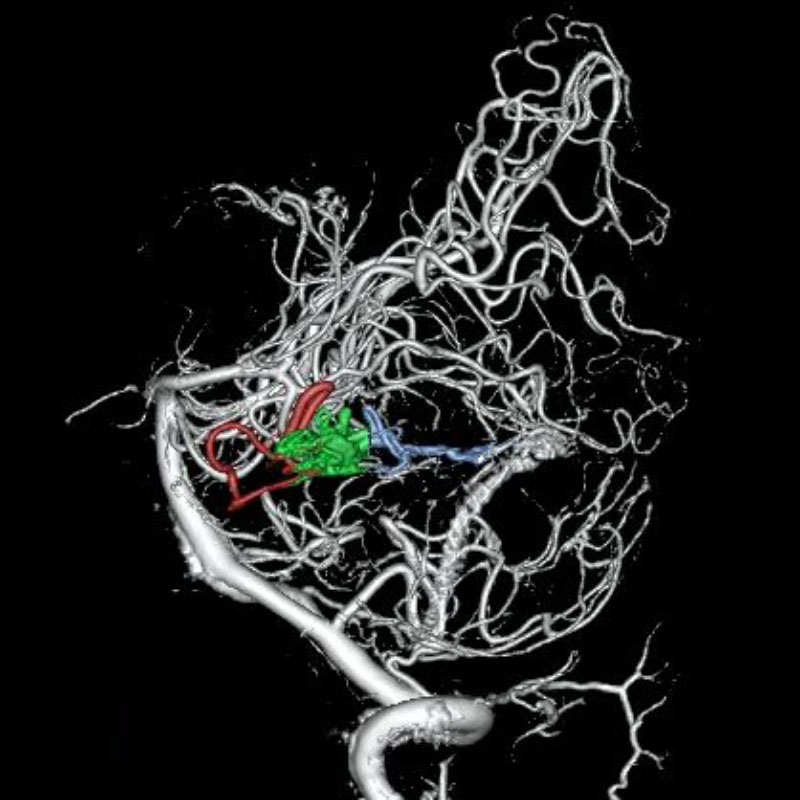

脳動静脈奇形

血管塞栓術

松田/濵田